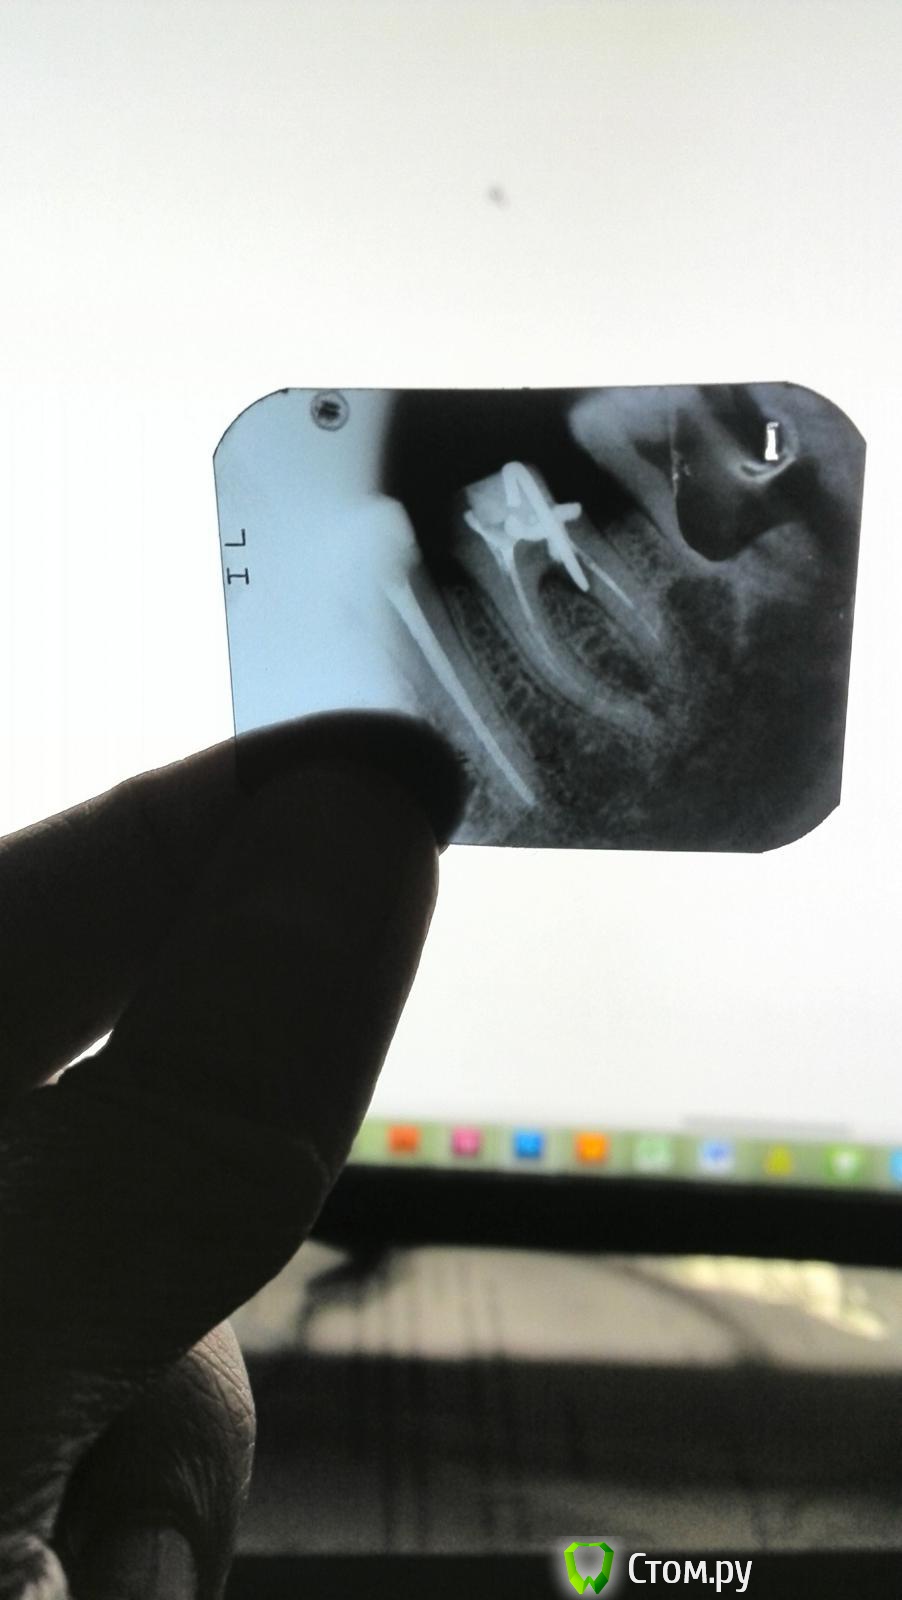

Jonatan Опубликовано 4 сентября, 2014 Поделиться Опубликовано 4 сентября, 2014 Здравствуйте!Прошу уважаемых специалистов прокомментировать ситуацию - завтра идти ставить коронку.Обратилась с запломбированным еще год назад, мертвым, отколовшимся зубом для постановки коронки.Каналы были пройдены резорциновой пастой. Зуб не беспокоил, но разваливался, распираемый пломбой.Широкий канал врач немного расшил и ввел туда арматуру, после запломбировал и обточил, снял слепки.Зуб начал дико болеть в тот же день: пульсация, мозжение по десне; острая, часами не проходящая боль после надавливания-настукивания, тяжесть в области зуба, боль даже при изменении положения тела. Постепенно уменьшилась, но осталась сильная боль при надавливании на зуб, которая проходит минут через десять.На снимке похоже, что арматуринка перфорировала корень???и видно воспаление под дном зуба между корней (в зоне предполагаемой перфорации). Есть ли смысл ставить коронку?Правомерны ли опасения по поводу перфорации?Врач ничего толком не говорит, хотя снимок его смутил.Заметил только, что один конец арматурины "возможно, травмирует десну, отсюда боль",и что "под зубом воспаление, но пока, наверное, постоит". Ссылка на комментарий

shishok Опубликовано 5 сентября, 2014 Поделиться Опубликовано 5 сентября, 2014 Я тут видела темы, по поводу запечатывания перфораций под микроскопом.Это нереально по какой-то причине? В данной ситуации слишком большой дефект(перфорация). Ссылка на комментарий

samsonov Опубликовано 6 сентября, 2014 Поделиться Опубликовано 6 сентября, 2014 Я тут видела темы, по поводу запечатывания перфораций под микроскопом.Это нереально по какой-то причине?[/quoteЗапечатывание " свежих" перфораций даёт лучший прогноз, инфицированный " старый" дефект - большая проблема.( 1 Ссылка на комментарий